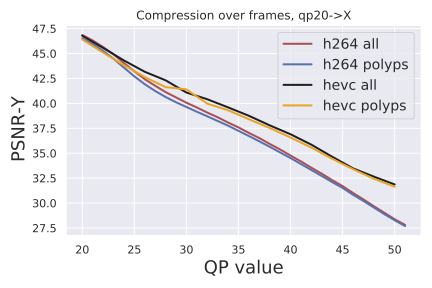

Compression metrics: We evaluate frame quality using two standard image metrics: PSNR-CbCr and PSNR-Y. PSNR is the standard "Peak Signal to Noise Ratio" derived from the mean squared error between pixels in the original frame and the compressed frame. The value of the pixels depends on the type of PSNR computation:“CbCr" corresponds to PSNR between chroma of the frames, and “Y" corresponds to PSNR between luminance of the frames.

Compression quality: Figure 1 (middle) shows the compression rate versus frame quality distribution for H264 and HEVC. Importantly, we see that H264 and HEVC compress the most medically relvant frames statistically significantly worse: treating each QP value separately, a two-sided Kolmogorov-Smirnov test between distribution of PSNR-CbCr shows that the frame quality is lower for polyp frames than for all frames. For each QP value, , , H264 (HEVC) maximum p-value over all tests is (), mean test statistic (). For the same test with PSNR-Y, see the Appendix. Figure 2 top two rows show the lowest quality compressed frames inside the body according to PSNR-CbCr, with and without polyps (for the absolute worst quality compressed frames, see the Appendix).

See Figure 4 for compression quality as a function of QP value instead of compression rate, as well as quality measured by PSNR-Y. Furthermore, the Kolmogorov-Smirnov tests on PSNR-Y show the same behavior: treating each QP value separately, a two-sided between distributions shows that the frame quality is lower for polyp frames than for all frames (for each QP value, , , H264 PSNR-Y max p-value is , mean test statistic , HEVC PSNR-Y maximum p-value over all tests is , mean test statistic ). This result holds for each QP value between 20 and 51.